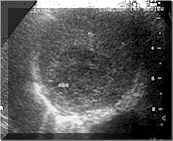

Very early stage :

In the initial stage, cell death occurs but entire dissolution and liquefaction is not complete as the contents are not liquid. This may be termed as solid abscess. On ultrasound these lesions are usually small and probably are the most challenging as compared to the other stages of the liver abscesses. The margins of the abscess may be ill defined, the abscess is hypoechoic as compared to the surrounding liver. However, there is no true liquefaction at this stage and therefore there is poor or no posterior acoustic enhancement. The demarcation between the abscess and the surrounding liver is also poor (see Picture1).

Picture1. Early abscess [1].

At this stage, the differential diagnosis of fat spared area in a fatty liver or an early neoplastic lesion have to be considered.